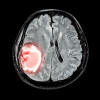

Manajemen agnosia dilakukan sesuai dengan penyakit yang mendasarinya. Pada pasien stroke iskemik, dapat dilakukan trombolisis dan pemberian obat-obatan antiplatelet, statin, serta antihipertensi. Pada kondisi tumor otak, terapi pembedahan, radioterapi, serta kemoterapi diberikan sesuai dengan indikasi.[1,8]